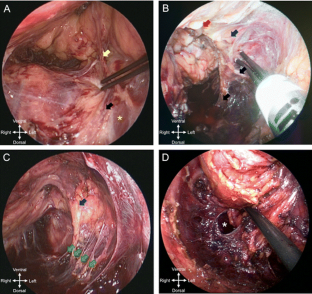

Sparing the extrinsic autonomic innervation of the internal anal sphincter during total mesorectal excision is important for the preservation of anal sphincter function. This study electrophysiologically confirmed the topography of the internal anal sphincter nerve supply during laparoscopic-assisted transanal minimally invasive surgery for total mesorectal excision.

This prospective study was conducted at two large multispecialty referral centers. Six patients (five males and one female) aged between 45 and 65 years with low rectal cancer (≤5 cm from the anal verge) were enrolled. Surgery was performed under electric stimulation of the pelvic autonomic nerves with observation of the electromyographic signals of the internal anal sphincter.

The minimally invasive transanal surgical approach enabled advantageous visualization of the pelvic autonomic nerves in all patients. In particular, extrinsic innervation to the internal anal sphincter near the levator muscle was consciously spared under electrophysiological confirmation. The evoked absolute electromyographic amplitudes of the internal anal sphincter during transanal minimally invasive surgery were significantly lower than the initial results of the laparoscopic approach [3.7 μV (interquartile range 2.4; 5.7) vs. 4.3 μV (interquartile range 3.1; 8.6); p = 0.002]. Five key zones of risk for pelvic autonomic nerve damage were identified. No complications occurred.

The electromyographic results of this preliminary study indicate advantages for sparing the internal anal sphincter innervation during transanal minimally invasive mesorectal dissection considering the specific in situ neuroanatomical topography.